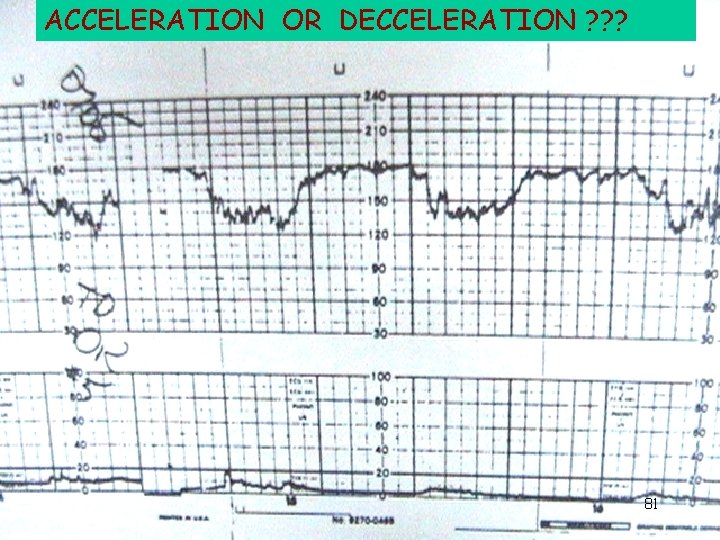

ACCELERATION OR DECCELERATION ? ? ? 81